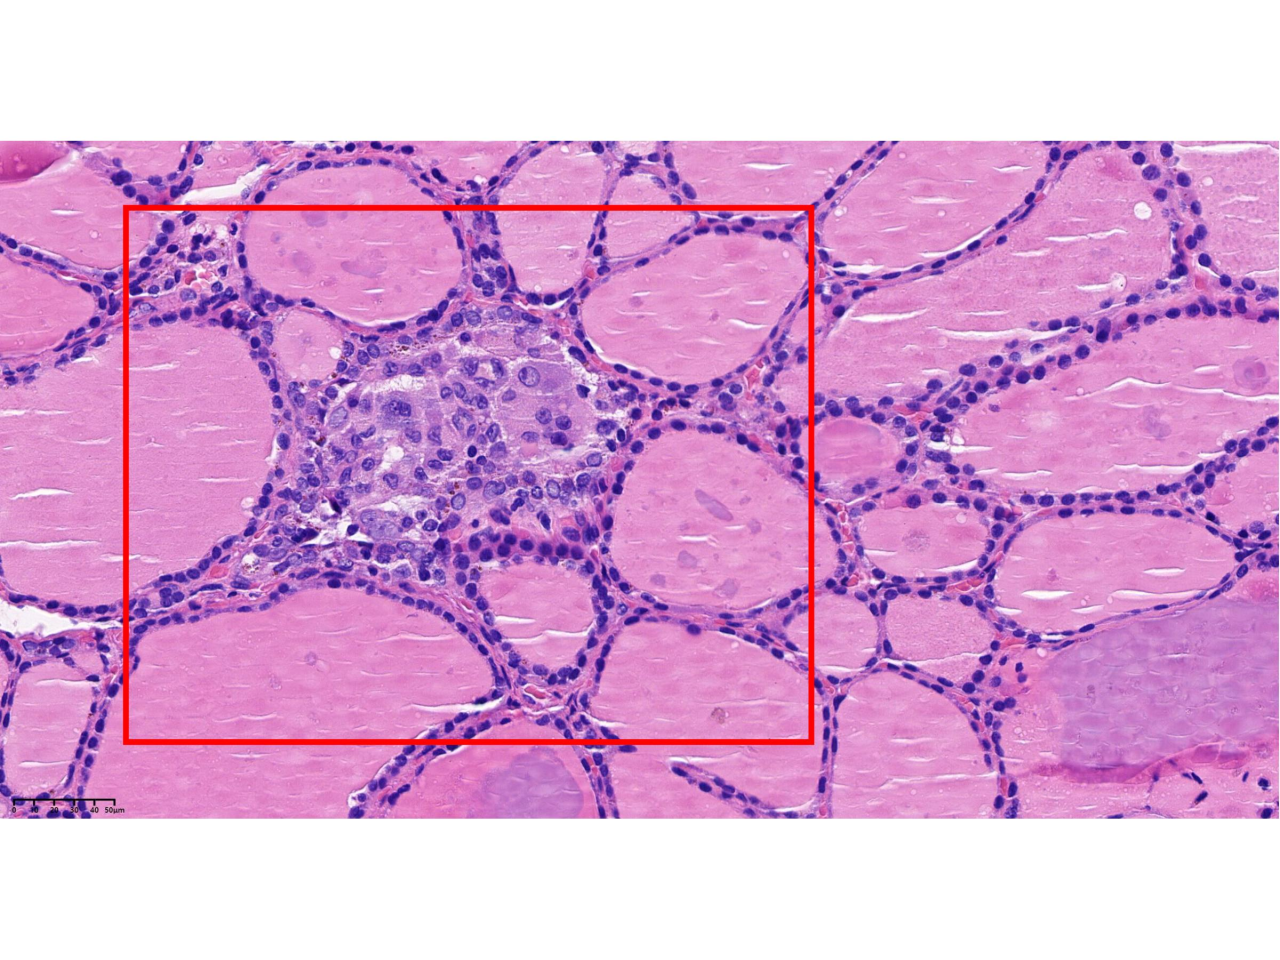

手术如期进行,左侧甲状腺及峡部顺利切除。切除标本立即送往病理科进行术中冰冻检查。显微镜下,病理科医生初步给出诊断:结节性甲状腺肿伴腺瘤样结节。看似风平浪静,但病理科团队的职业敏感让他们没有轻易按下“确认键”——他们深知,医学的世界里,平静之下或许暗流涌动。 术后,喉前淋巴结标本按常规送检。在免疫组化的辅助下,一个不幸的结果浮出水面:淋巴结出现转移!作为恶性肿瘤的重要标志,淋巴结转移意味着原发癌灶必然存在,可这个“罪魁祸首”却仿佛人间蒸发,在组织中隐匿得无影无踪。一场与微小癌灶的“捉迷藏”就此展开。 “必须找到它,给患者一个明确诊断!”病理科贾薇主任果断决定,将术中送检的左侧甲状腺及峡部剩余组织全部取材,共补取24个蜡块,将所有蜡块逐一制片,在显微镜下开启“地毯式搜索”。 时间一分一秒流逝,病理科团队的目光在无数细胞间穿梭游走。终于,在一张切片中,一个微乎其微的身影闯入视野——直径仅0.4毫米,比针尖还要细小,却在显微镜下清晰呈现出甲状腺乳头状癌的典型特征。就是这个“潜伏者”,正是淋巴结转移的元凶!最终,病理报告明确:左侧甲状腺乳头状癌。 甲状腺乳头状癌直径<1cm时,从前被称为“微小癌”,早期往往没有典型症状,极易被忽视或误诊。而此次发现的癌灶仅为0.4毫米,这样的“针尖级”病灶,不仅考验着病理医生的专业水准,更需要极致的细心与责任心。任何一个细微的疏忽,都可能导致漏诊,影响患者的治疗时机和预后。 从术中冰冻的初步判断,到术后淋巴结转移后的执着追查,这场与“隐形杀手”的较量,最终以病理科团队的严谨与坚持画上句号。他们用“宁繁勿简”的态度、“锱铢必较”的精神,践行着“敬佑生命、救死扶伤”的医者初心。在肉眼不可见的微观世界里,他们以责任为灯、以匠心为刃,为患者的生命健康筑起一道坚不可摧的防线。 什么是甲状腺癌 一、发病机制:甲状腺癌是遗传与环境共同作用的结果。遗传方面,基因突变导致癌变;环境方面,辐射是高危因素,碘摄入异常也会刺激细胞增生,增加癌变的可能性。病理科可以检测基因突变,从基因层面了解发病的原因。 二、常规筛查方法:超声是首选筛查手段,能显示甲状腺形态、结构及结节特征,初步判断疾病的良恶性,但最终需要做病理活检确诊;影像学检查可观察肿瘤侵犯范围,辅助制定方案。 三、病理诊断方法: 1.细针穿刺细胞学检查:对超声怀疑恶性的结节,用细针穿刺制成涂片,观察细胞形态判断良恶性,该检查创伤小、准确率高。 2.术中冰冻检查:手术中组织送检,30分钟内快速判断病变良恶性,为手术方案提供即时依据。 3. 常规组织活检:这是病理诊断的“金标准”。通过手术切除的病变组织,制成切片,在显微镜下观察细胞和组织结构,直接确诊病变的性质、类型和分化程度,是最终确诊的关键依据。 4.免疫组化检查:常规组织活检难以确诊时,利用特异性抗体检测特定蛋白质表达,明确肿瘤类型、分化程度和预后。 5.分子病理检测:检测肿瘤组织基因突变、融合基因等,为甲状腺癌精准分型、预后评估和靶向治疗提供依据,如检测BRAF基因突变判断恶性程度和复发风险。 四、预后情况:甲状腺癌有很多种类型,最常见的是乳头状癌,大约占80%-90%。它通常性格“温和”,生长缓慢,但却像这次发现的“针尖癌”一样,有早期转移的可能。经过规范的治疗,大部分甲状腺癌的预后都很好,10年生存率可以超过90%,因此它常被称为“懒癌”。患者的预后情况与肿瘤的分期、有无转移、以及患者年龄密切相关。我院病理科通过对肿瘤的精准分型、分期和分级,为临床医生提供了一份详尽的“病理报告单”,从而为患者量身定制最科学的随访计划和治疗方案。 供稿|病理科 郭婧薇 编辑|朱思佳 编审|于 磊 王晓民 权江宏 杨 涛